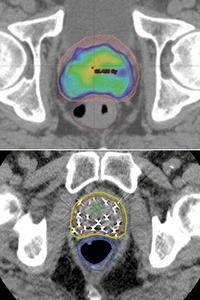

放射線治療は、体の外から前立腺に集中して放射線を照射する外照射があります。そのうち前立腺の形状に合わせて照射する方法を、特に強度変調放射線治療(IMRT)といいます=写真上=。前立腺の形に合わせて放射線が照射されます。色がついている部分が強く照射されているところで、前立腺の下にある直腸にできるだけ照射されないようになっています。

もう一つは、放射線を放出する直径1ミリ、長さ10ミリの金属を60個ほど前立腺内に埋め込む小線源治療です=写真下=。赤い線で囲った部分が前立腺です。前立腺の内部に金属が埋め込まれています。その金属から放射線が出て前立腺に影響を与えます。この放射線は2カ月もすれば、体外に与える影響も少なくなり、1年たてば放射能はなくなります。